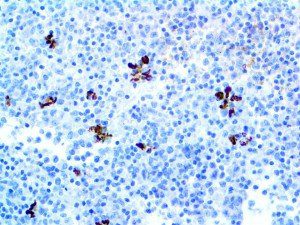

The first cytokines released are interleukin 1β (IL-1β) and tumor necrosis factor-α (TNF-α), which attract a variety of circulating white blood cells (WBCs) to the infection site, including neutrophils, monocytes, macrophages, and natural killer (NK) cells. This response, along with the antipathogenic chemicals released by these cells (i.e., complement), comprise the innate immune response. These cells directly attack the invading pathogen and also release additional cytokines, chief among them interleukin-1 and 6 (IL-6). IL-6 is essential for invoking the adaptive immune response, which calls T-cells, B-cells, and T helper (Th) cells to the infection site. IL-6 also stimulates further recruitment, proliferation and activation of macrophages.

It is the ICU physician who is most likely to witness one of the deadliest manifestations of the abnormal immunological response, the cytokine storm syndrome (CSS). This response is also referred to by some as the cytokine release syndrome (CRS). CSS is characterized by continuous activation and expansion of macrophage and lymphocyte populations, which secrete large amounts of cytokines, causing the cytokine storm. This massive cytokine release is akin to hemophagocytic lymphohistiocytosis (HLH) disease, a syndrome characterized by initial unchecked and persistent activation of cytotoxic T lymphocytes and NK cells.